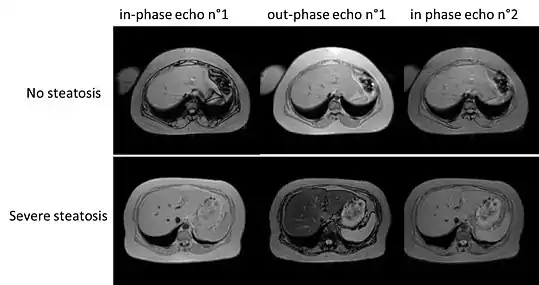

On magnetic resonance imaging, multiecho gradient echo images can be used to determine the percent fat fraction of the liver.[13] The different resonance frequencies between water and fat make this technique very sensitive and accurate. Acquisition of echoes in "in phase" and "out phase" conditions (pertaining to the relative phases of the fat and water proton contingents) enables to obtain a signal proportional to the water and fat contingent, or a signal proportional to the water minus the fat contingent. These signal intensities are then algebraically combined into a percent fat. More recent techniques take into account experimental noise, signal decay and spectroscopic properties of fat. Numerous validation studies have demonstrated excellent correlations between the steatosis level quantified at MRI and the steatosis levels semi-quantitatively and quantitatively determined on liver biopsies (reference methods). Several MRI vendors offer automated calculation of percent fat with acquisition sequences no longer than a single breath hold.

Liver steatosis (fatty liver disease) as seen on MRI. Multiecho MR sequence in a healthy liver (top row) and a liver with severe steatosis (bottom row) are shown. In the healthy liver, the signal does not vary much in the different echoes. In the steatotic liver, the signal varies greatly between in and out phase echoes. Algebraic combination of these images can be used to accurately quantify liver steatosis.

Liver steatosis (fatty liver disease) as seen on MRI. Multiecho MR sequence in a healthy liver (top row) and a liver with severe steatosis (bottom row) are shown. In the healthy liver, the signal does not vary much in the different echoes. In the steatotic liver, the signal varies greatly between in and out phase echoes. Algebraic combination of these images can be used to accurately quantify liver steatosis. Abdominal ultrasonography with the liver and kidney side by side (left image) may give a false impression of hyperechogenic liver, so it's preferably done with the organ borders facing the ultrasound probe (right image, of the same case).